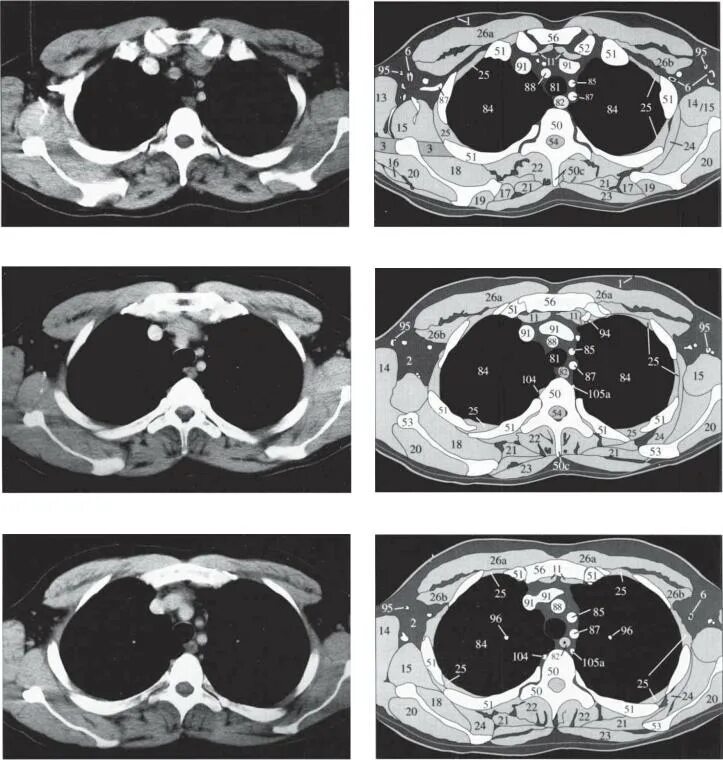

Какой кт